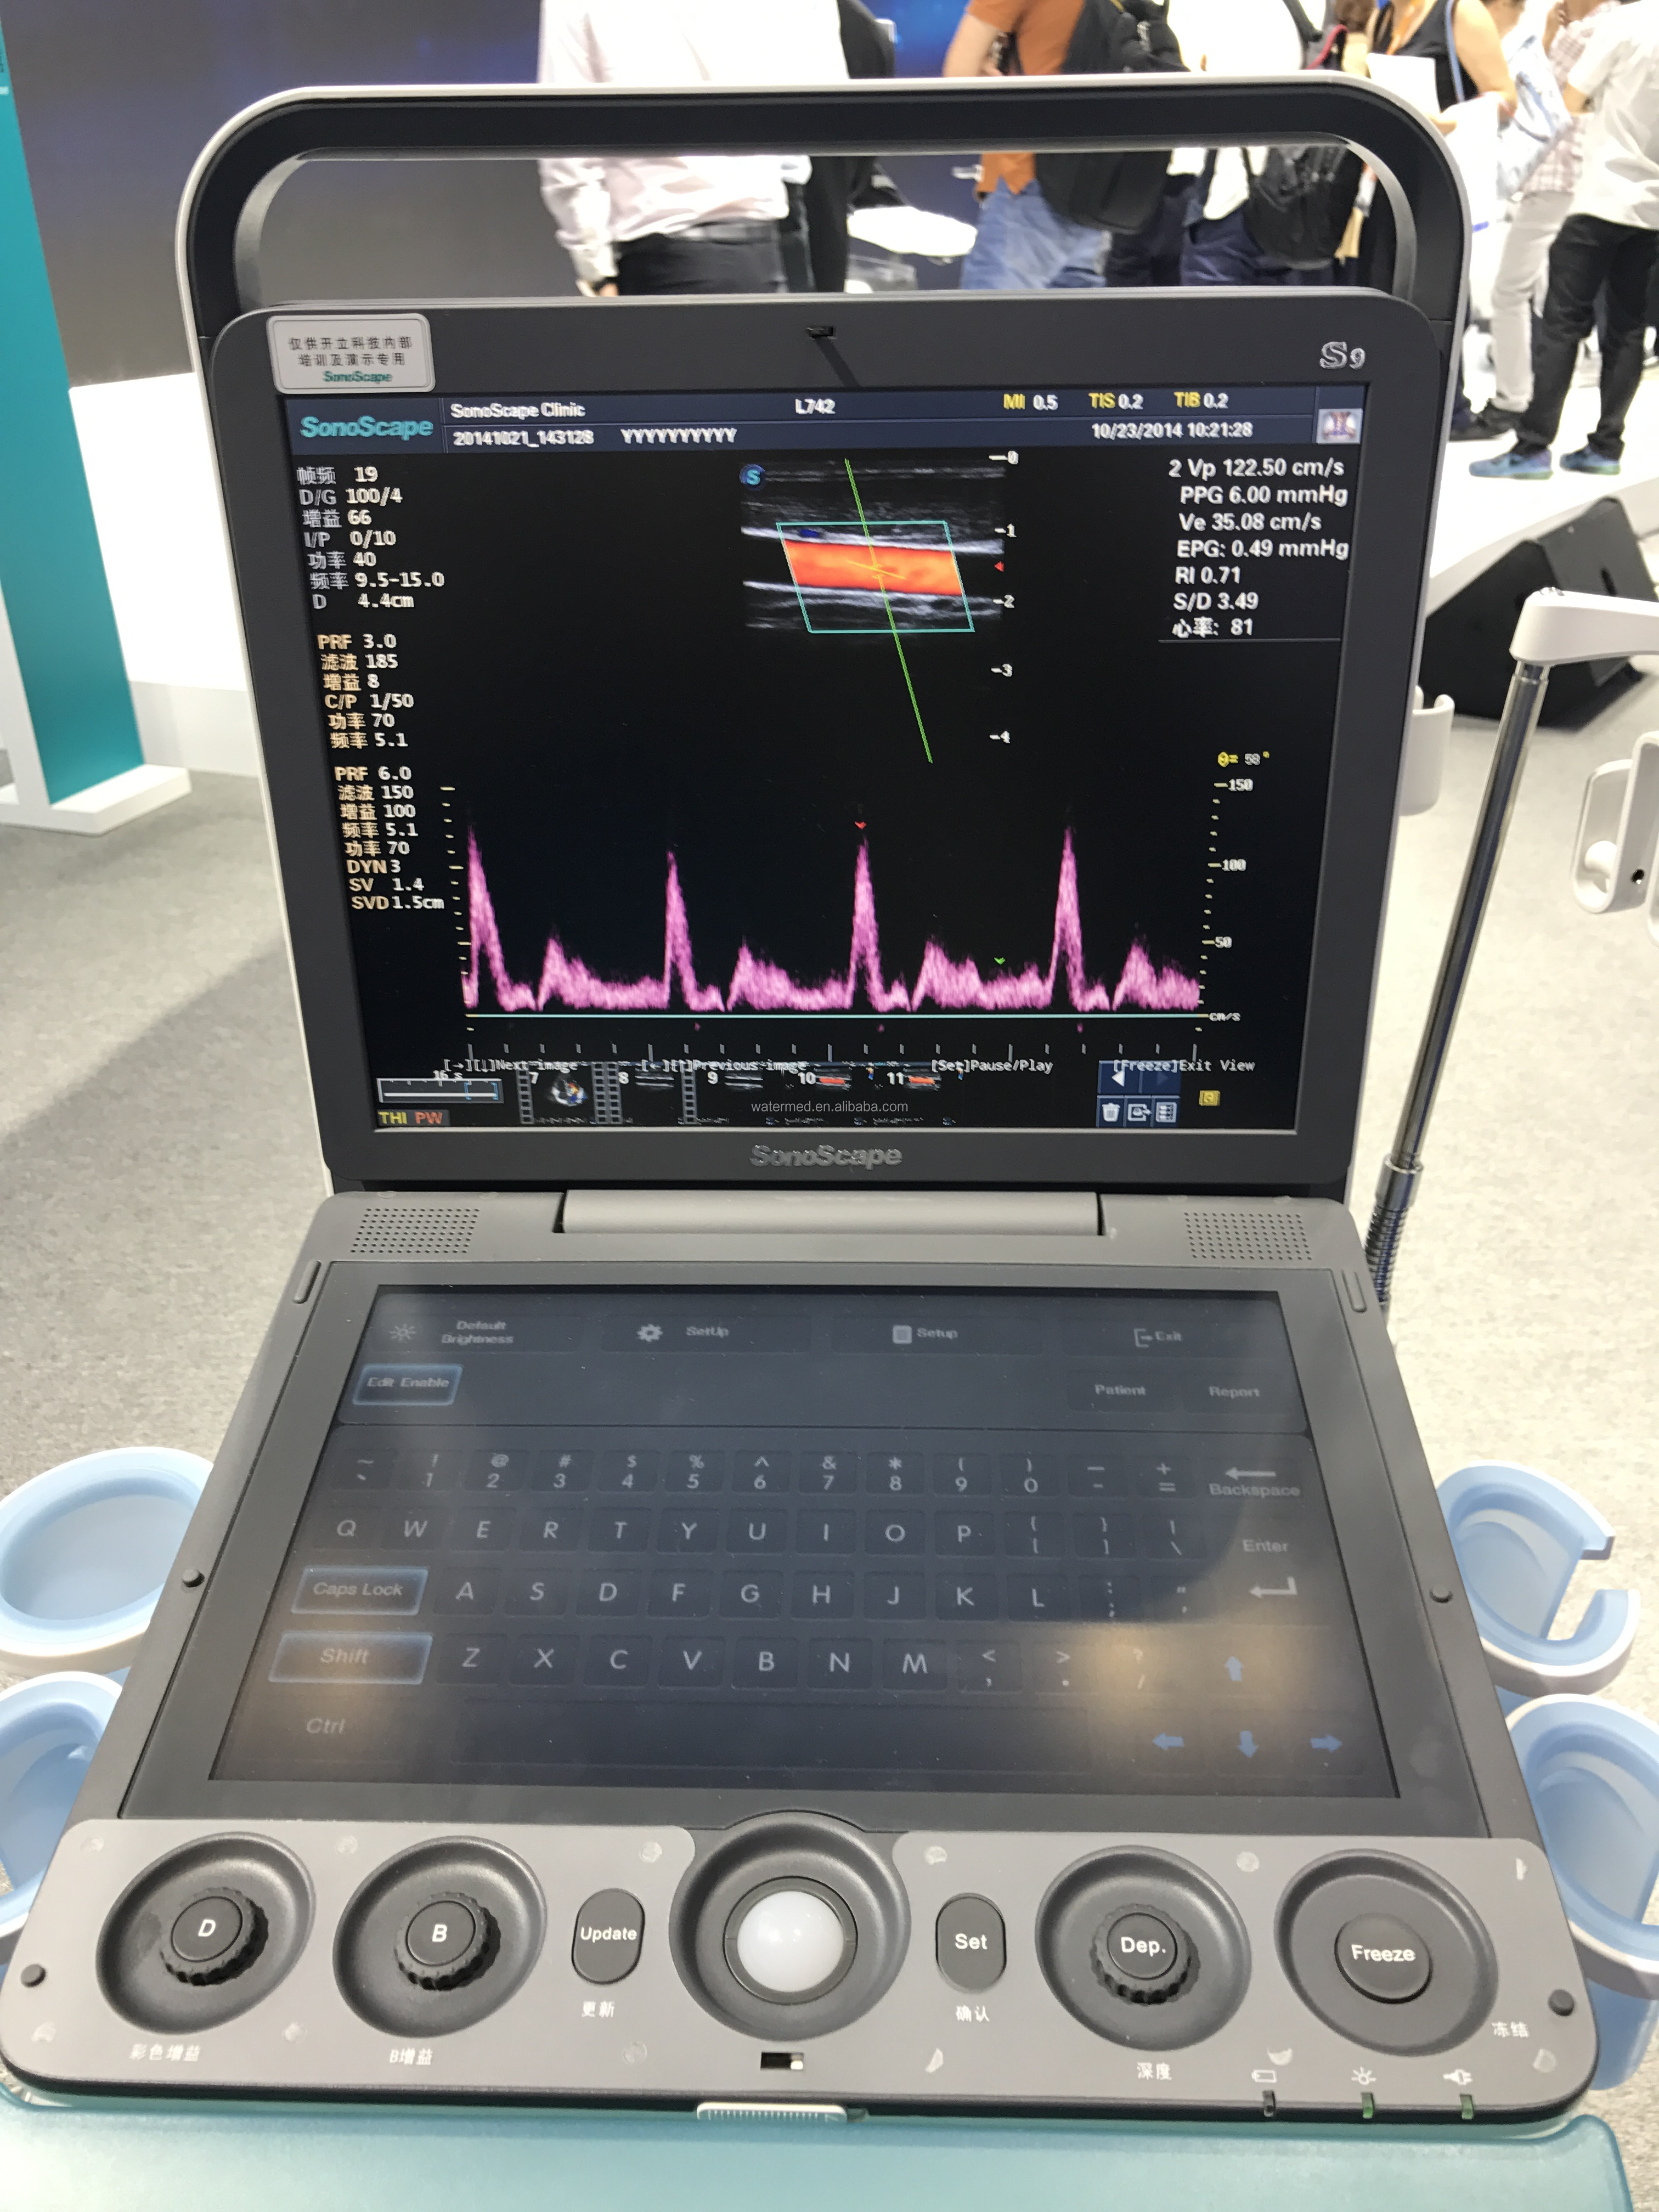

Portable 3D 4D Color Doppler USG&Sonoscape S9

Portable 3D 4D Color Doppler USG&Sonoscape S9

SonoScape has been in the field of ultrasound since releasing the first portable color Doppler ultrasound system. From this dedication, a large number of ultrasound technologies have emerged, especially in hand-held systems. Out of this dedication, the S9 was released as a powerful and versatile imaging platform with a futuristic design. Small in size and wide in application, the S9 is suitable for Cardiology, Radiology, Abdominal, Obstetrics, Small Parts and Urology, providing the best solution for ultrasound imaging with outstanding performance.

pulse inversion harmonic imaging

Harmonic signals are adequately preserved without degrading acoustic information, which allows the S9 to image high-level details and improve contrast resolution by reducing noise and clutter in the visualization of subtle lesions, small sites, blood vessels, etc.

Harmonic signals are adequately preserved without degrading acoustic information, which allows the S9 to image high-level details and improve contrast resolution by reducing noise and clutter in the visualization of subtle lesions, small sites, blood vessels, etc.

S9 is equipped with a high-density phased array probe to meet the needs of high frame rate and high resolution for cardiac imaging. Thanks to the high sensitivity of SonoScape color Doppler mapping, the S9 can provide an accurate cardiac diagnosis beyond your imagination.

S9 is equipped with a high-density phased array probe to meet the needs of high frame rate and high resolution for cardiac imaging. Thanks to the high sensitivity of SonoScape color Doppler mapping, the S9 can provide an accurate cardiac diagnosis beyond your imagination.